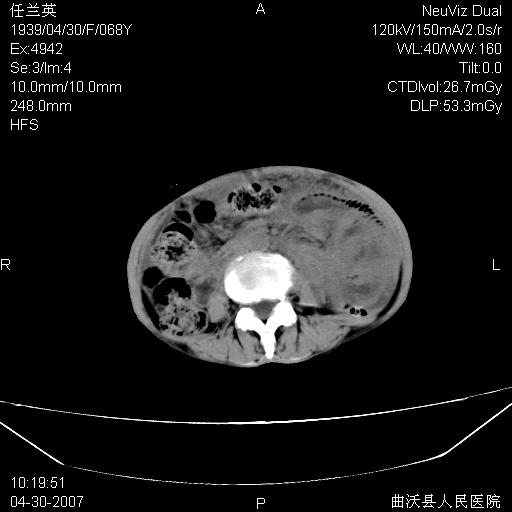

患者,女,68岁,感觉腹部憋涨发硬数天,查b超发现左盆腔有囊性肿物和少量腹水,行ct检查

1.考虑卵巢肿瘤并腹腔广泛性转移可能性大;

2.腹盆腔少量积液。

支持左侧卵巢恶性肿瘤伴网膜、腹膜广泛转移。

网膜、腹膜广泛转移考虑来源于左侧卵巢癌可能性大。不除外来源于消化系的肿瘤。

难的一见 典型 - 网膜饼  冰冻骨盆 可以当教学片了